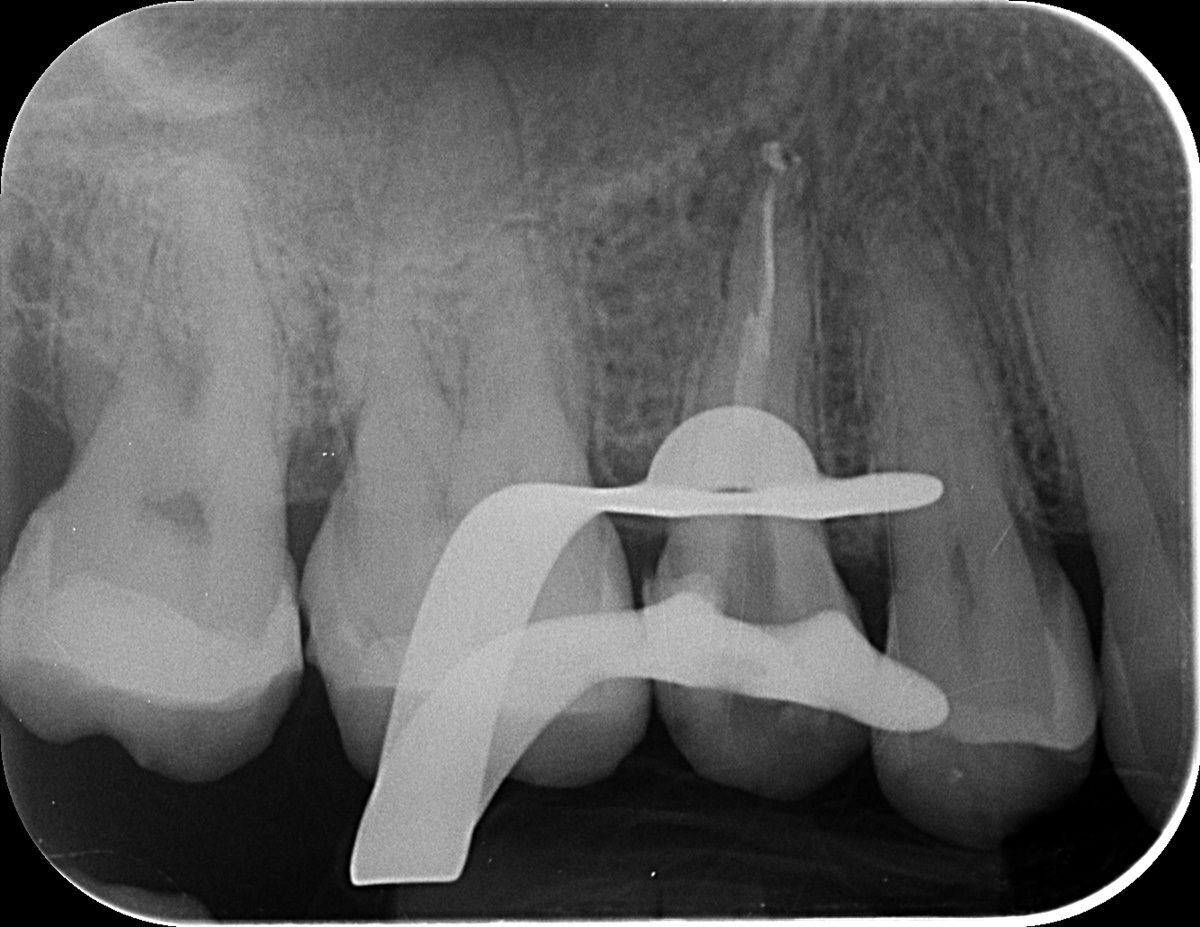

Az érintett jobb felső ötös fogról a páciens már egy kis fogfelvétellel érkezett. A kezelés megkezdése előtt a röntgen megtekintésekor feltűnt, hogy valószínűleg nem egy, hanem két betört fragmentumról van szó. Ezek a fogak gyakran két csatornával rendelkeznek, illetve ebben az esetben egy érdekes variációval: a két csatornának közös vége van. Ilyenkor az egymás felé ívelő gyökércsatornák meglehetősen görbék lehetnek - tipikus helyei a tűtöréseknek.

mikroszkópos gyökérkezeléssel megmentett fog: a bent rekedt fragmentumok eltávolítása 1

Először a szájpadlás felőli gyökércsatornában tártuk fel a tűt. Óvatosan, a megfelelő technikát alkalmazva sikerült eltávolítani a kb. 4 mm-es darabot. Ilyenkor készítünk egy kontrollröntgent, hogy lássuk, valóban nem maradt bent semmi az eltávolított tűből. Ekkor vált biztossá a gyanúnk, van még egy műszer a fogban.

mikroszkópos gyökérkezeléssel megmentett fog: a bent rekedt fragmentumok eltávolítása 2